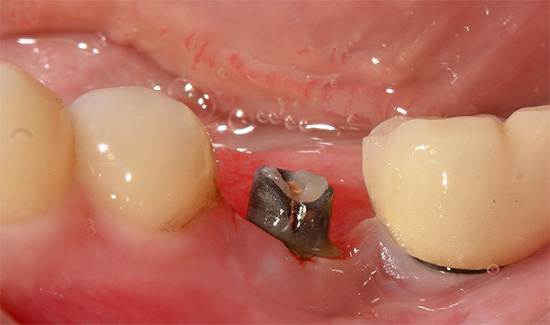

Na próxima etapa do implante basal, a instalação real dos implantes é realizada pelo método de punção ou incisão (ou imediatamente após a extração do dente). Uma punção torna possível realizar todo o procedimento sem suturar e é adequada para pessoas com gengivas enfraquecidas e inflamadas.

Na foto - periimplantite (inflamação do osso e tecidos moles na área do implante):